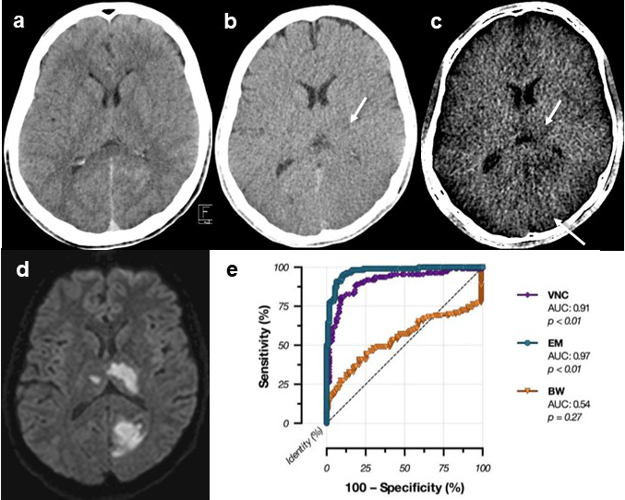

The detection of acute cerebral infarction is crucial in order to decide on further treatment. By comparison with conventional CT, early infarctions can be identified better with dual-energy CT (Fig. 2). A recent research project aims to predict infarction development prior to its visualisation, by using radiomics features in dual-energy CT datasets.